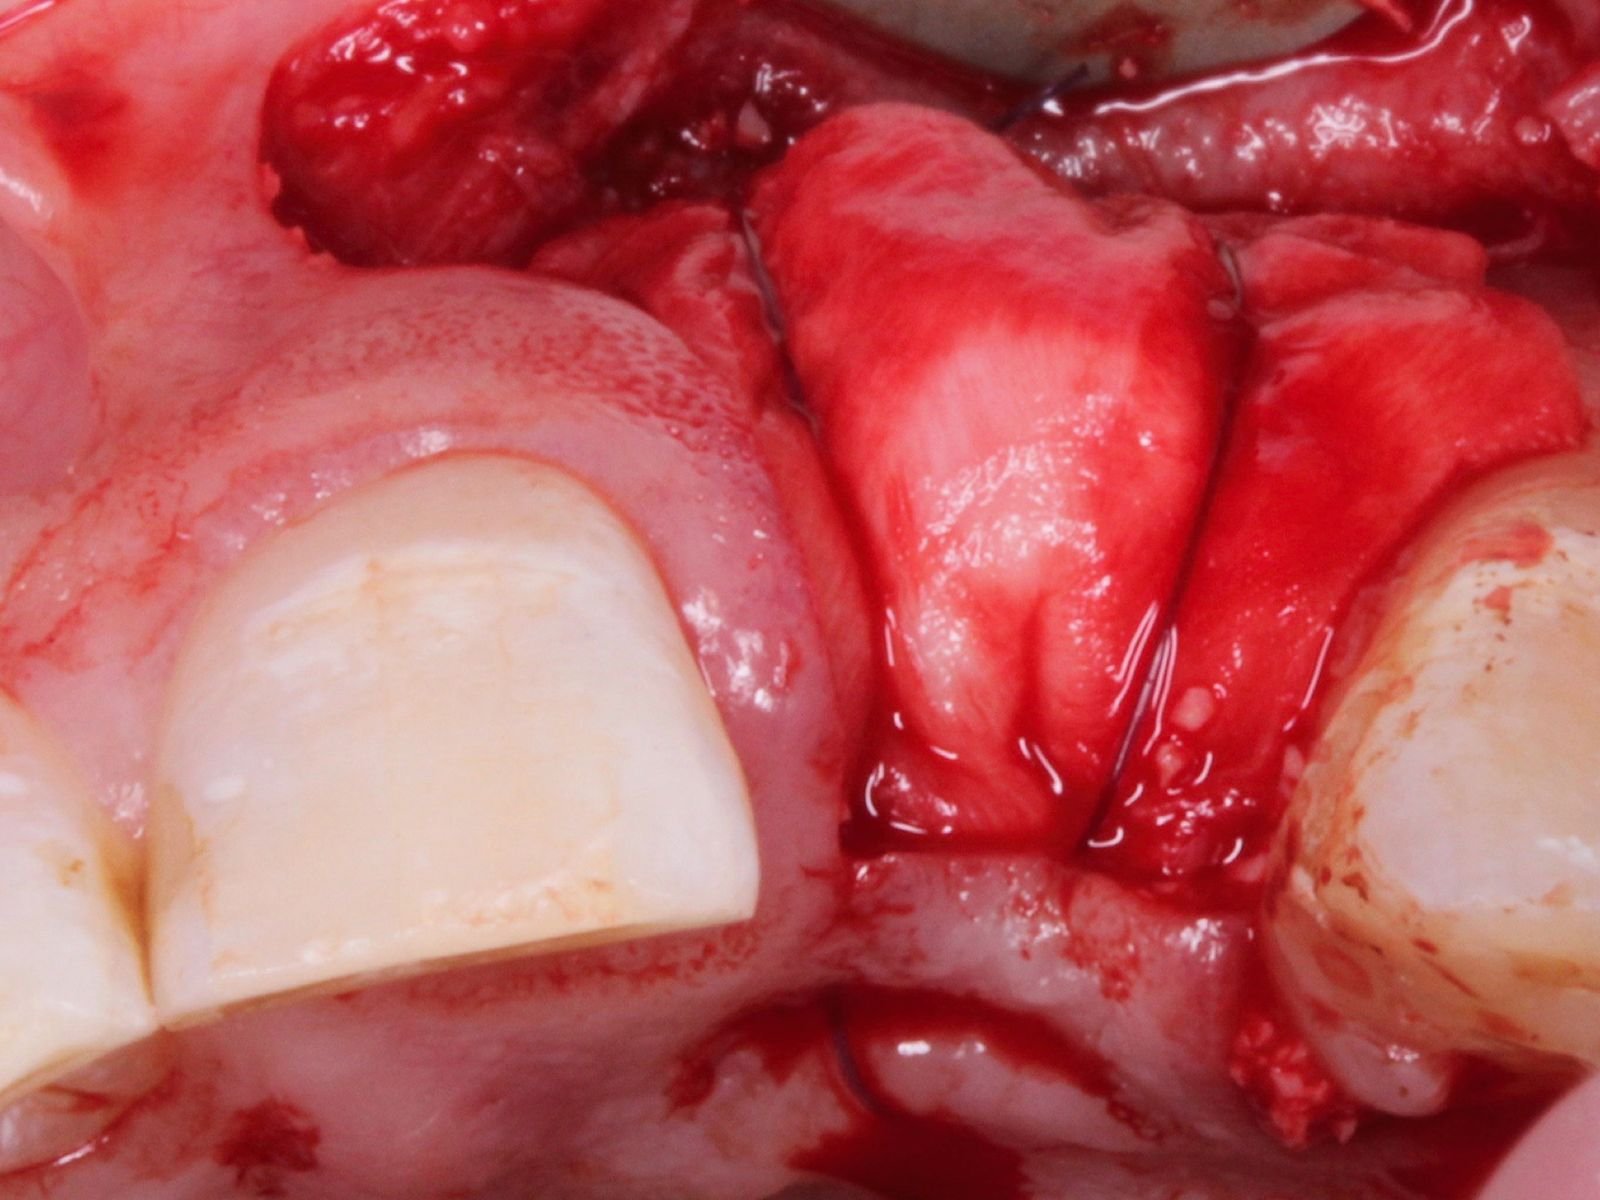

• Comprehensive case assessment and treatment planning for periodontal and peri-implant soft tissue defects

• Grafting indications for teeth and implants, particularly addressing recession and mucogingival defects

• Understand the principles of graft harvesting and management of the recipient and donor sites

• Recognise, manage and prevent complications associated with soft tissue grafting

• Understand basic and advanced suturing techniques

This course will teach you the fundamentals of soft and hard tissue grafting. Beginning with a brief revision of the periodontium, you will then learn how to identify patients who would benefit from such surgeries, as well as safe and effective ways to manage them. This includes suture technique and flap design, soft and hard tissue graft materials with specifications on the qualities and handling of each, and post-procedural management. Medico-legal advice and managing complications will also be discussed to help you gain a comprehensive view of this field.